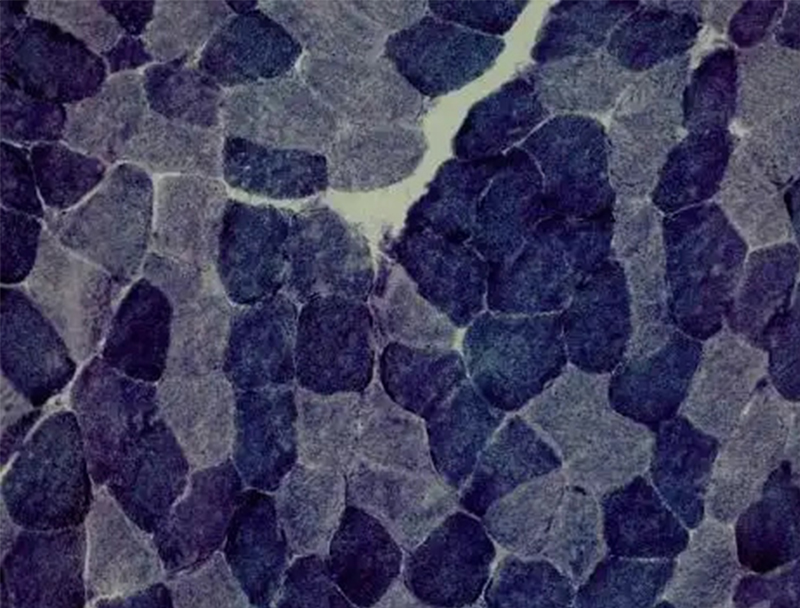

以下是关于 ATP 酶染色的相关介绍:基本原理ATP 酶是一种水解酶,可催化 ATP 分解产生能量。在 ATP 酶染色中,常用的是钙钴法,其原理是 ATP 酶水解 ATP 为 ADP 和磷酸,磷酸与钙离子在酶活性部位结合形成无色的磷酸···